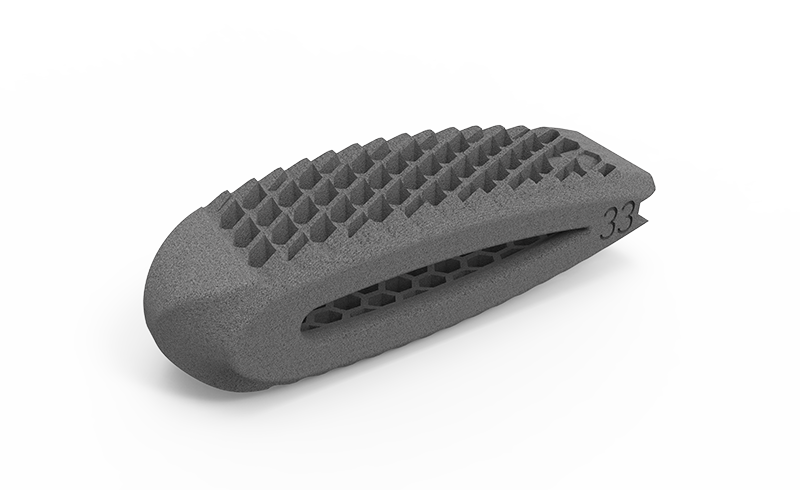

zurückDeltacorCages

Cages

Alle Modelle nun mit der patentierten hygroskopischen Struktur. Diese Kapillarwirkung beeinflusst das Einwachsverhalten positiv ohne Verwendung von autologem Knochen.

zurückMOONY-SLMTLIF aus Titan

MOONY bietet durch seinen schwenkbaren Universaleinbringer ein sicheres und einfaches Einbringen des Cages. Das patronenförmiges Design, sowie Finnen auf der Grund und Deckplatte des Implantates, lassen den Cage sehr elegant in den interkorporellen Bereich gleiten.